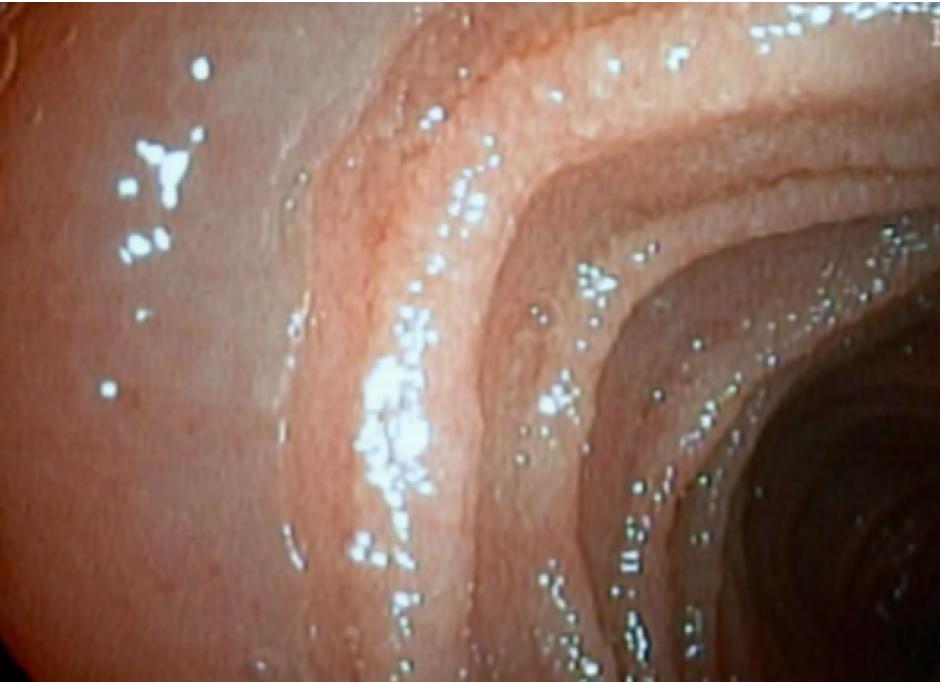

顺行双气囊小肠镜(DBE)显示,从空肠(图B)到回肠(图C),肠壁弥漫性水肿,并可见淡黄色的绒毛状黏膜。

图B